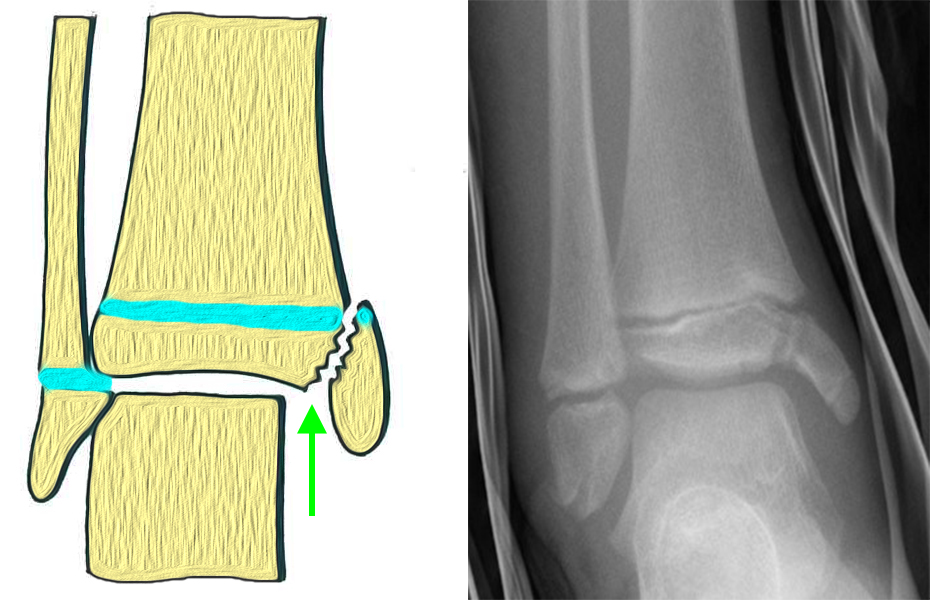

Fugengelenkfrakturen können die Wachstumsfuge durchkreuzen (Abbildung 16a), ohne oder nur mit minimaler Beteiligung der Fuge sehr weit medial liegen (Abbildung 16b) oder durch die Fuge auslaufen (Abbildung 16c). Relevant für die Wachstumsprognose ist weniger die Form der Fraktur, sondern das Alter des Patienten zum Zeitpunkt des Traumas sowie das Ausmaß der Schädigung der Wachstumsfuge, wobei eine Korrelation mit dem Ausmaß der Dislokation besteht.